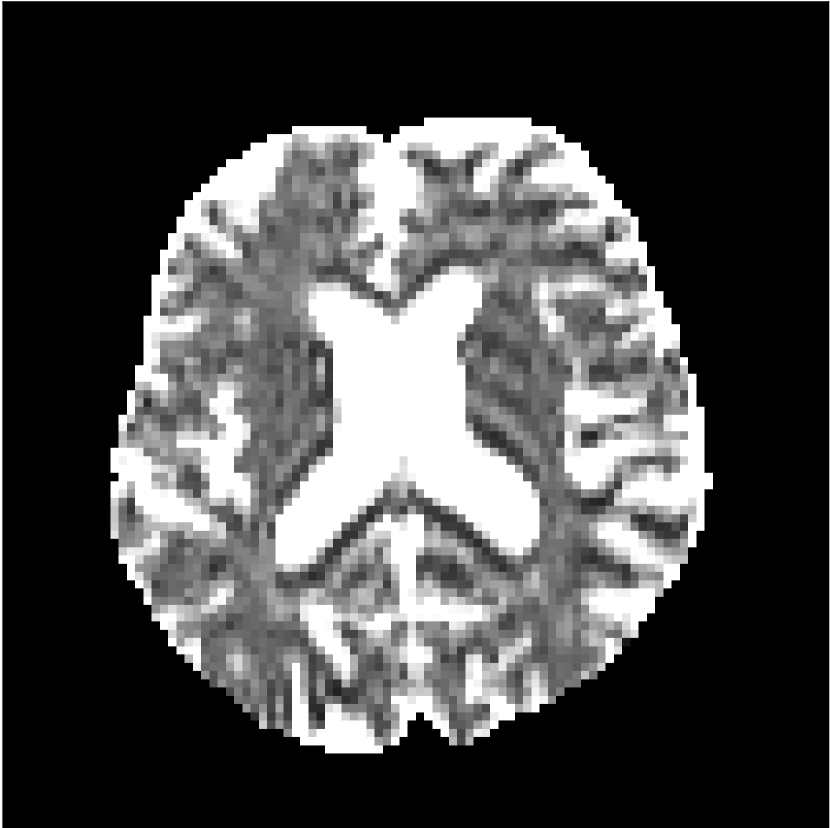

Figure 9 shows parameter maps for the different methods without partial Fourier (No PF) and with 5/8ths partial Fourier (5/8 PF). Mean diffusivities calculated from the raw DWI data (Raw) show notable noise and Gibbs ringing artifacts, while this is substantially removed with the state-of-the-art (SoA) method. However, the state-of-the-art method begins to lose its ability to compensate for the Gibbs ringing and resolution loss when partial Fourier is utilized in the acquisition. The effects of partial Fourier increases are primarily evident in the enlargement of the lateral ventricles and the presence of black lines in the vicinity of the lateral ventricles. The MCNN model is able to compensate somewhat for the ringing effects, but begins to introduce substantial artifacts at the 5/8ths partial Fourier factor, whereas the CCNN model continues to give high-quality mean parameter maps across all PF factors.

Raw

SoA

MCNN

Standard PF

CCNN

MK

Figure 9: Parameter maps from various methods (with CSF masks for FA and MK). At the top are shown the b=0𝑏0b=0 images from Raw, state-of-the-art (SoA), MCNN, standard partial Fourier, and CCNN methods. Rows 2 and 3 show results for mean diffusivity, rows 4 and 5 show results for fractional anisotropy, and rows 6 and 7 show results for mean kurtosis. The SoA method and both deep learning methods perform well without partial Fourier acceleration; however, at the 5/8ths partial Fourier factor, substantial artifacts are present for all methods other than the CCNN method.

Similar trends are observed in the other diffusion parameter maps.